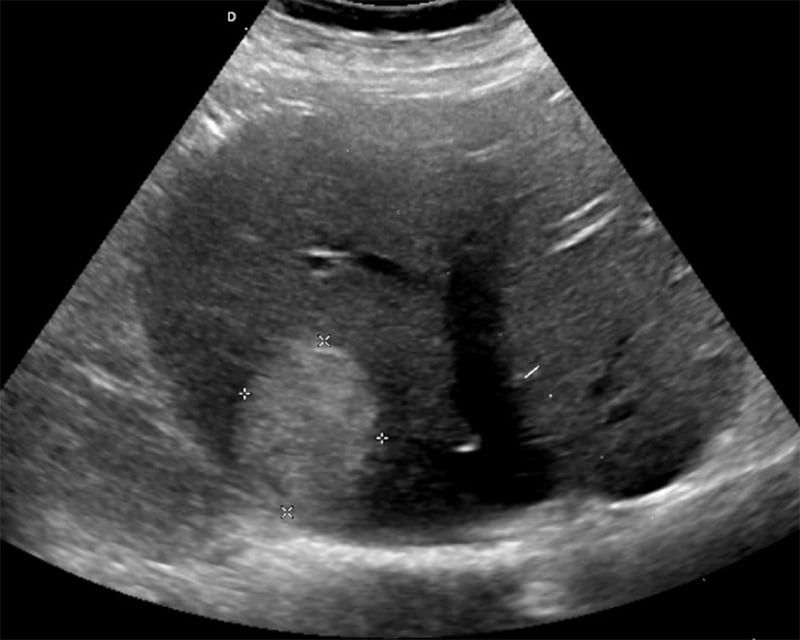

Figures 24B & 24C. Large pyogenic liver abscess with heterogenous material swirling inside the lesion, measuring >11cm in the long dimension (B) and >5cm in the shorter dimension (C).